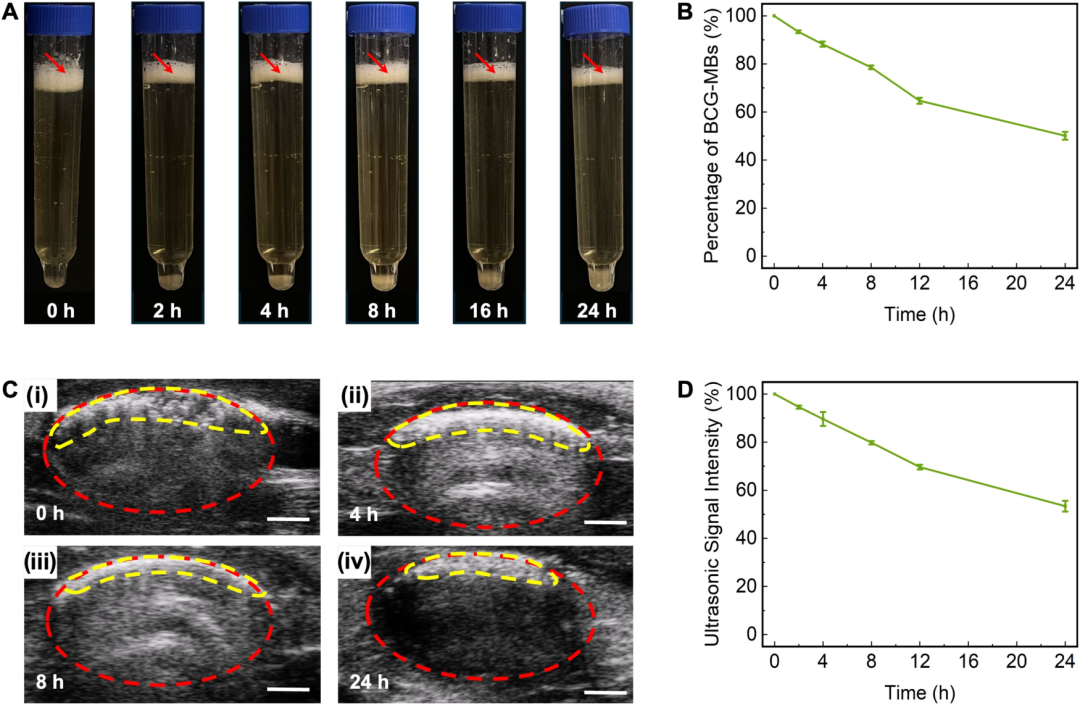

在实验验证过程中,研究团队通过多种技术手段全面评估了BCG-MBs的性能。体外实验表明,BCG-MBs在尿液中表现出优异的漂浮能力,24小时后仍有超过50%的微气泡保持漂浮状态;而在模拟排尿的条件下,BCG-MBs能够持续释放BCG,维持治疗有效浓度达24小时以上。更为重要的是,在原位膀胱癌SD大鼠模型中,与传统BCG治疗相比,BCG-MBs治疗组展现出显著增强的治疗效果:不仅肿瘤生长受到更有效的抑制,还诱导了更持久的免疫反应,表现为IL-2等关键细胞因子水平的持续升高,同时未观察到明显的系统毒性。这些结果充分证明,通过延长BCG在膀胱内的作用时间,可以显著提升免疫治疗的疗效。

图 在尿液收集管和SD大鼠膀胱中表征BCG-MBs的漂浮和滞留特性